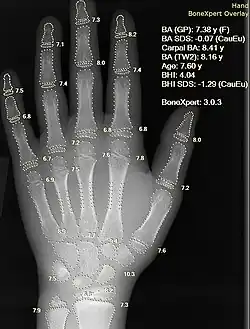

Вычисление медицинских изображений и информатика визуализации

Информатика медицинских изображений и компьютеризация медицинских изображений разрабатывают вычислительные и математические методы для решения проблем, связанных с медицинскими изображениями и их использованием для биомедицинских исследований и клинической помощи. Эти области направлены на извлечение клинически значимой информации или знаний из медицинских изображений и компьютерный анализ изображений. Методы могут быть сгруппированы в несколько широких категорий: сегментация изображений, регистрация изображений, физиологическое моделирование на основе изображений и другие.